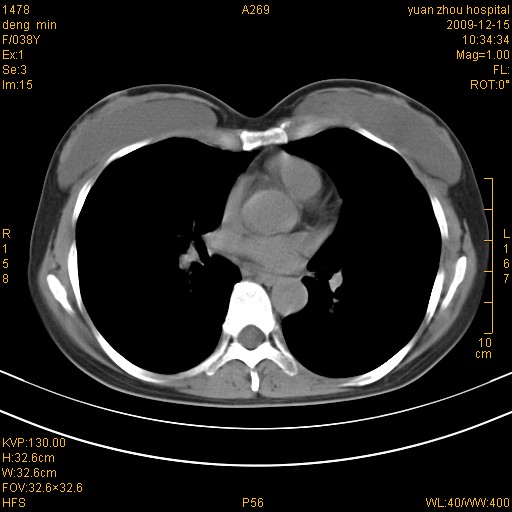

右肺中下叶、左肺上叶舌段及左肺下叶支气管扩张合并感染。